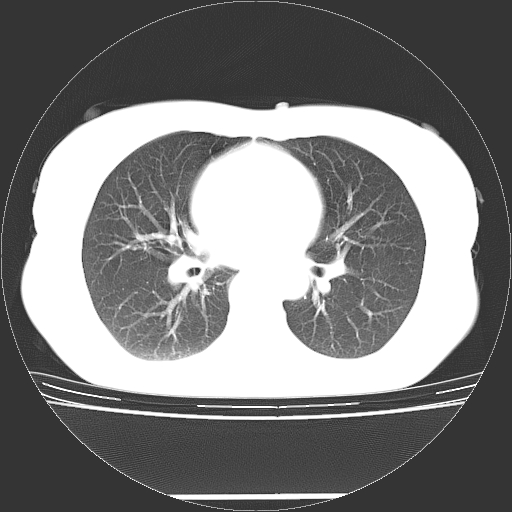

标题: CT27224:女,43岁,体检发现左肺下叶结节影。 [打印本页]

女,43岁,体检发现左肺下叶结节影。

左下肺外带胸膜下见孤立实性均匀密度结节影,边缘光整,增强呈渐进性强化,病灶吴分叶征及毛刺征象;支持硬化性血管瘤。